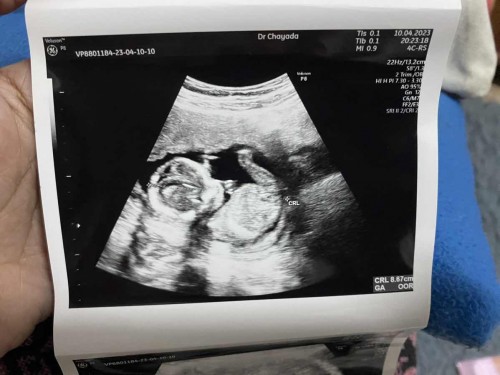

8 กันยาค่ะ แพ้หนักมาก ยันเกือบ16สัปดาห์เลยค่ะ กินอะไรไม่ได้แม้แต่น้ำ ข้าวไม่กินเหม็น กินเส้นๆพอได้ค่ะ กินอะไรก็ออกหมด พอเริ่มดีขึ้นกับข้าวจืดกินไม่ได้ ชอบกินเผ็ด ชอบน้ำหวานน้ำปั่นขนมหวาน สิวมาเต็มจัดหนัก รักแร้ดำ ผิวคล่ำขึ้น พึ่งซาวด์มาวันนี้ ได้ลูกสาวค่ะ95%เลย มีแต่คนคิดว่าจะได้ลูกชาย 😅